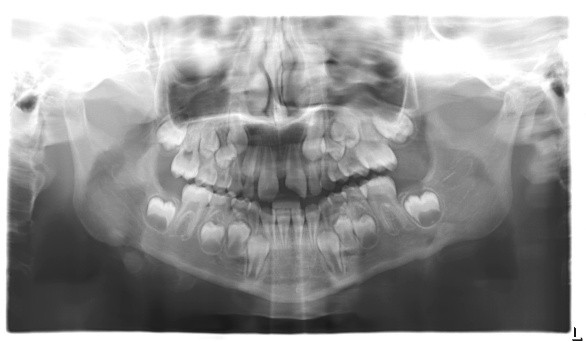

Which of the following is true regarding the following panoramic radiograph?